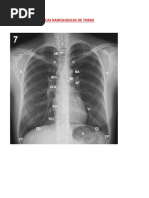

RX DE TÓRAX: Es el método más sencillo y de mayor utilidad diagnóstica en la valoración del paciente con trauma de

tórax. Sirve para la valoración de los pulmones y de todas las estructuras que lo rodean

La radiografía cervical lateral, tórax anteroposterior y pelvis son básicas en cualquier politraumatizado en Urgencias.

Proyecciones: Generalmente se toma la radiografía en proyección A-P en posición supina, pero si el paciente se puede

movilizar, se debe tomar la proyección vertical posteroanterior.

Lo mejor es tomarlo PA si el paciente se puede movilizar, si no, se toma AP, el problema con esta proyección es que

las estructuras se agrandan

¿Cuánto se agranda el mediastino? ¿Cuáles son los signos radiológicos de la disección de aorta? Ensanchamiento del

mediastino mas de 12 cm cuando la placa fue tomada en bipedestación. Osea que el paciente estaba acostado. Si pasa

mas de 12 cm el ensanchamiento del mediastino SE SOSPECHA UNA LESION.

¿Que se busca?

1- Partes blandas.

● Hematomas.

● Enfisema subcutáneo.

● Cuerpos extraños.

● Pliegues cutáneos.

2- Partes óseas (fracturas).

● Clavícula, descartar lesión de arteria o

vena subclavia y plexo braquial.

Costillas 1ª, 2ª y 3ª, lesiones traqueo

bronquial, ruptura de aorta y grandes

vasos.

● Costillas 10ª y 11ª, rotura esplénica y/o

hepática.

● Esternón, contusión cardiaca.

3- Pleura.

● Hemotórax, no se evalúa en decúbito

dorsal.

● Neumotórax. Casquete apical, rotura

de aorta y grandes vasos.

4- Mediastino.

● Neumomediastino, (neumotórax diferido, rotura traqueobronquial, rotura de esófago, barotrauma por VM.)

● Ensanchamiento mediastinal, (rotura aórtica, hematoma por rotura de vasos venosos, artefacto por decúbito.)

● Desviación de la tráquea a la derecha.

● Elevación y desviación a la derecha del bronquio mayor derecho.

● Depresión del bronquio mayor izquierdo. Desviación del esófago (SNG)

5- Parénquima.

● Imagen precoz, contusión pulmonar.

● Imagen diferida, neumonitis broncoaspirativa, embolismo graso, hematomas pulmonares. Atelectasias, rotura

traqueobronquial, cuerpos extraños.

6- Diafragma. Sospechar su rotura. Elevación, o pobre identificación

NOTA: Siempre revisar que esté bien tomada (escápulas afuera, que se vean de 8-9 espacios intercostales, clavículas

equidistantes a apófisis espinosas vertebrales) y posterior a esto buscar si hay enfisema, fracturas, neumoperitoneo,

hemotórax, neumotórax- Idealmente revisar todo y por último lo que sospechamos que vamos a hallar en la

radiografía.